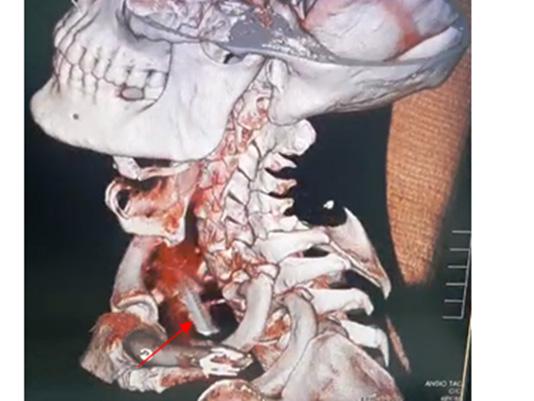

Trauma traqueal por migración de material de osteosíntesis de clavícula

Tracheal trauma due to migration of clavicle osteosynthesis material

Roly Ramos, Cristhian J. Guzmán, Rommer Ortega.............................................................................116-121